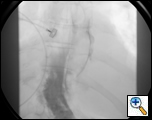

A 79 year-old female presented to an outside institution with a one day history of epigastric and retrosternal pain in the summer of 2005. She had no complaints of fever, emesis, hematemesis, retching, weight loss, odynophagia, or dysphagia. Her past medical history included hypothyroidism and stable coronary artery disease. She was thought to have acute cholecystitis, and seven days later developed respiratory distress and a chest X-Ray revealed mediastinal air and a right-sided pleural effusion. Computed tomography (CT) scan of the chest showed a large fluid collection around the distal esophagus tracking into the right chest, a possible intraluminal mass and air within the wall of the esophagus (Figure 1). A chest tube was placed in the right chest which drained culture-negative serosanguinous fluid. A gastrograffin swallow revealed an esophageal perforation with free-flow of contrast into the right chest (Figure 2). The patient was transferred to our institution with the diagnosis of esophageal perforation.

Figure 2: Gastrograffin swallow reveals free perforation of the esophagus with contrast flowing into the right chest.